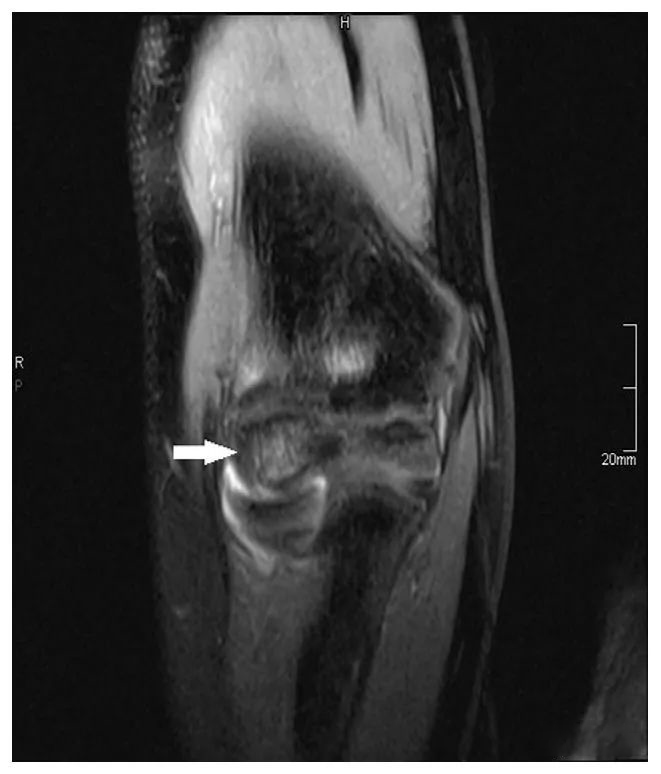

图四 (A) 冠状位 T1 和 (B) 矢状位 STIR 图像显示肱骨小头前正中部信号异常的病灶区 (箭头所示),但没有高的流体信号,所以病灶是稳定的。STIR 图像显示肱骨小头前方水肿。一名 13 岁的剥脱性肱骨小头骨软骨炎患者接受了螺钉固定。(C) 矢状位 STIR 图像显示完整的螺钉 (箭头),病灶区碎片稳定,位置满意。

图四